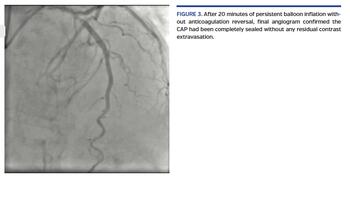

A short, 81-year-old woman presented with non-ST elevation acute myocardial infarction complicated with acute pulmonary edema. She was referred to urgent coronary angiography, performed via right distal transradial access, which is our default approach. The culprit left anterior descending (LAD) coronary artery was shown to have a long, tight, and calcified proximal-mid stenosis (Figure 1; Video 1), which was fixed by PCI with two drug-eluting stents (3 x 33 mm and 3.5 x 33 mm), requiring adequate pre- and postdilations with non-compliant balloons (2.5 x 20 mm and 3.5 x 20 mm, respectively). Surprisingly, the final angiogram showed an unexpected huge cavity spilling in-stent mid LAD perforation, with drainage to the left ventricle (Figure 2; Video 2). Promptly, the same postdilation NC 3.5 x 20 mm balloon was reinflated to 8 atm at the level of the CAP. After 10 minutes, there was some resolution. After a total 20 minutes of persistent balloon inflation without anticoagulation reversal, a final angiogram confirmed the CAP had been completely sealed without any residual contrast extravasation (Figure 3; Video 3). Transthoracic echocardiogram discharged pericardial effusion.

Type III cavity-spilling CAP (also called type IV CAP) is an unusual but dreaded complication, which can be conservatively managed with simple prolonged balloon inflation without compromising the final PCI result by anticoagulation reversal.